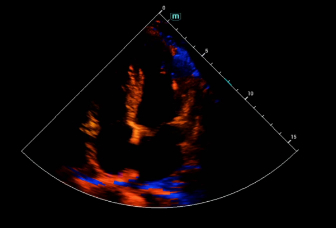

Consona presenta soluzioni nuove e concrete, che aiutano a effettuare diagnosi efficaci con semplicitĂ , rivolgendosi a un'ampia platea di pazienti. La serie mette a disposizione strumenti estremamente avanzati per rimanere all'avanguardia nella diagnosi cardiovascolare.

Galleria di immagini